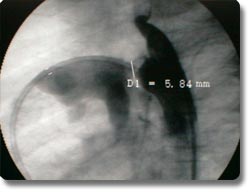

动脉导管未闭、房间隔缺损为先天性心脏发育缺陷,分别形成主动脉、肺动脉间及左右心房间的异常通道,传统治疗方式为外科开胸手术治疗。我科与国外同步开展了非手术经皮动脉导管封堵术及房间隔封堵术,用介入治疗方式矫正异常通道,手术时间30分钟左右,术后2天病员即可康复出院,疗效与外科开胸手术相同。 |